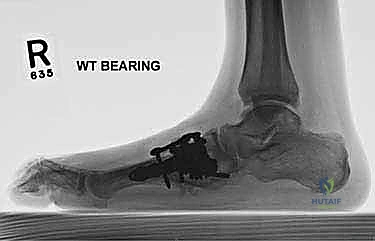

- الأشعة السينية أثناء الوقوف (Weight-bearing X-rays): وهي أهم أداة تشخيصية. الأشعة العادية والسرير فارغ لا تظهر المشكلة الحقيقية؛ يجب التقاط الأشعة والمريض يقف ليتحمل وزن الجسم، مما يظهر الانهيار الفعلي للمفاصل وتضيق المسافات بين العظام.

- الأشعة المقطعية (CT Scan): توفر صوراً ثلاثية الأبعاد للعظام، وهي ضرورية جداً للتخطيط الجراحي الدقيق وتحديد مدى التلف العظمي والزوايا المطلوبة للتثبيت.

6. التثبيت الصلب (Rigid Fixation)

لضمان التحام العظام لتصبح عظمة واحدة صلبة، يجب تثبيتها بقوة هائلة حتى لا تتحرك أثناء فترة الشفاء. يتم استخدام مسامير معدنية متطورة (Screws)، أو شرائح معدنية خاصة (Plates)، أو دبابيس طبية متخصصة (Staples) مصنوعة من التيتانيوم الآمن على الجسم.